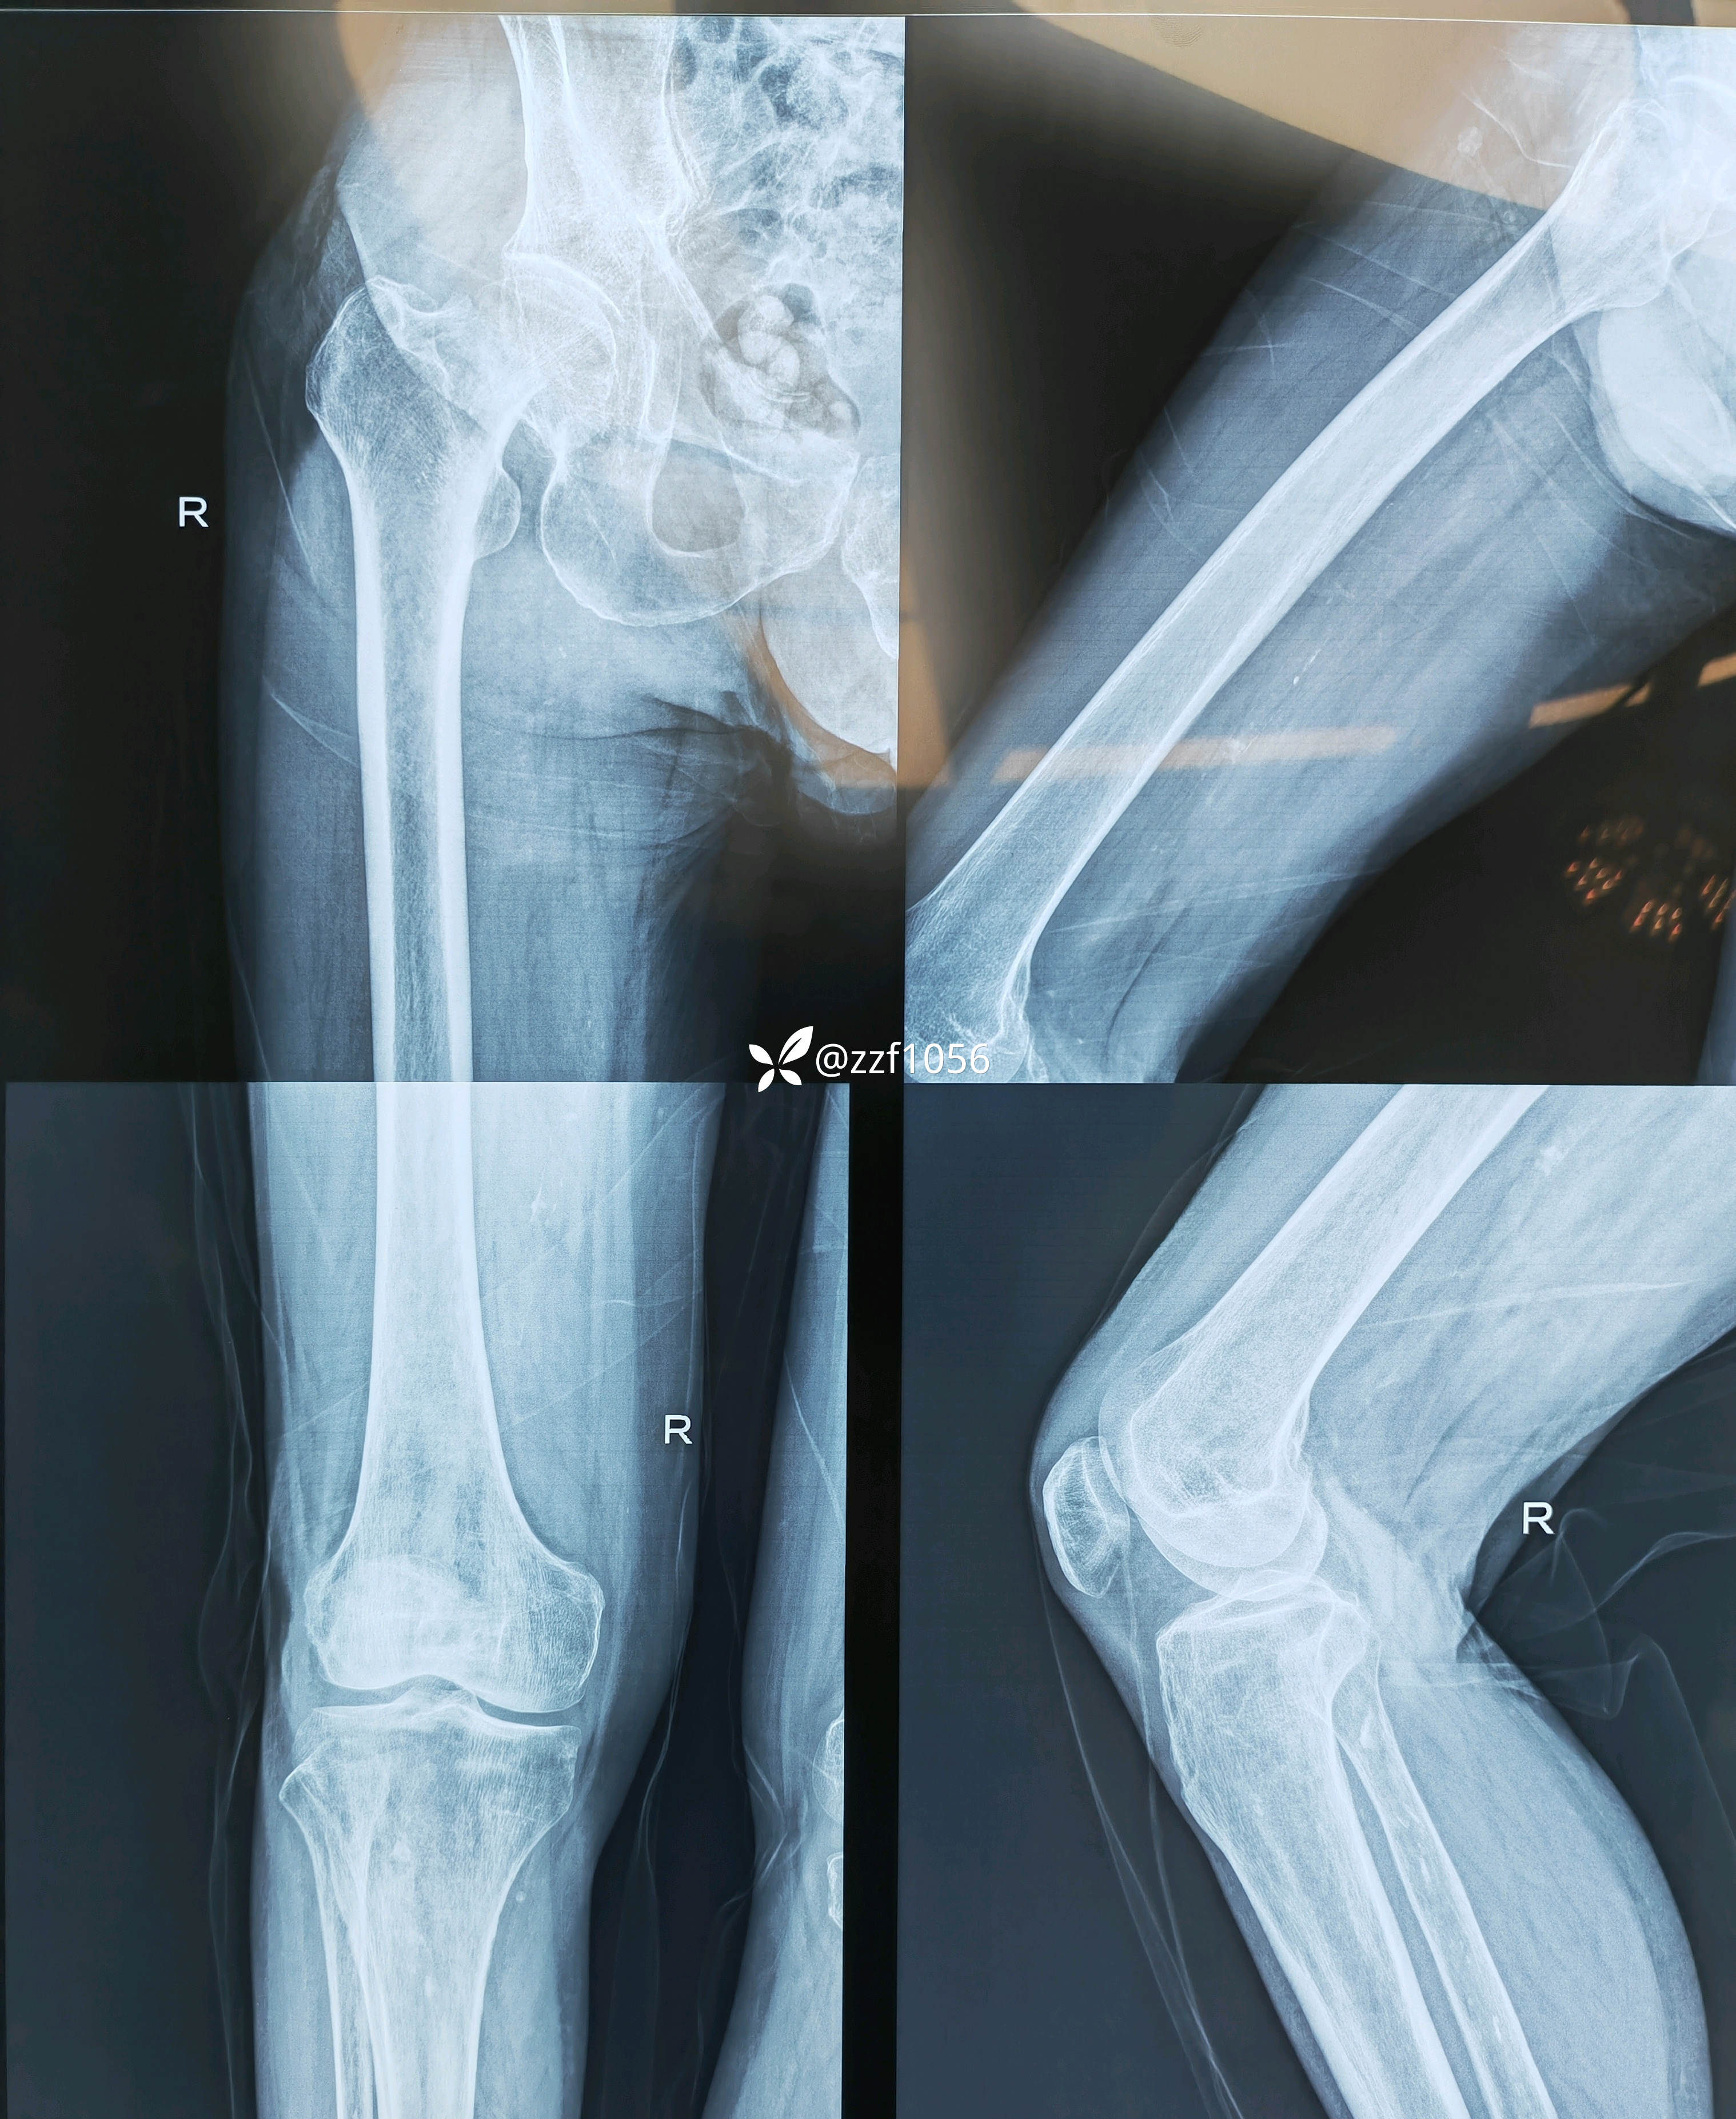

患者男80岁,摔伤右髋疼痛5天,入院。

5天前家里摔伤,附近医院摄片显示右侧股骨颈骨折,因身体状况不好回家保守治疗,疼痛无法耐受再次赴当地县医院就诊,评估身体状况后告知手术风险较大,后经熟人介绍转来我院就诊。

入院诊断:右侧股骨颈骨折

臀外侧还有压疮,采用什么入路呢?